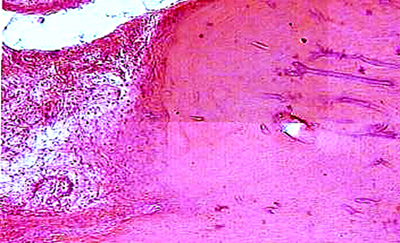

Общее представление о стволовой клетке, ее классификация и источники

Основные закономерности физиологической и репаративной регенерации

Роль стволовой клетки в остеотрепанации

Нарушение остеотрепанации